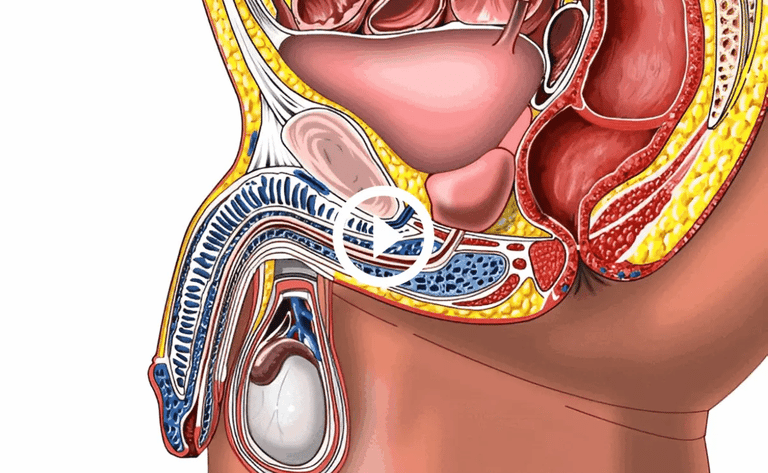

PROSTATE ADENOMAS

The proliferation of prostate tissue, formation of tumors, and "ganglia"